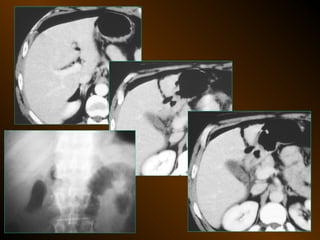

• X QUANG CẮT LỚP ĐIỆN TOÁN

TỤ DỊCH TRONGPHÚC MẠC • X QUANG QUY ƯỚC – Trong tiểu khung – Dọc hai bên hông – Giữa bụng • SIÊU ÂM – Phản âm trống, chuyển dịch – Lượng ít – Bản chất dịch • X QUANG CẮT LỚP ĐIỆN TOÁN – Mật độ – Vị trí – Nguyên nhân